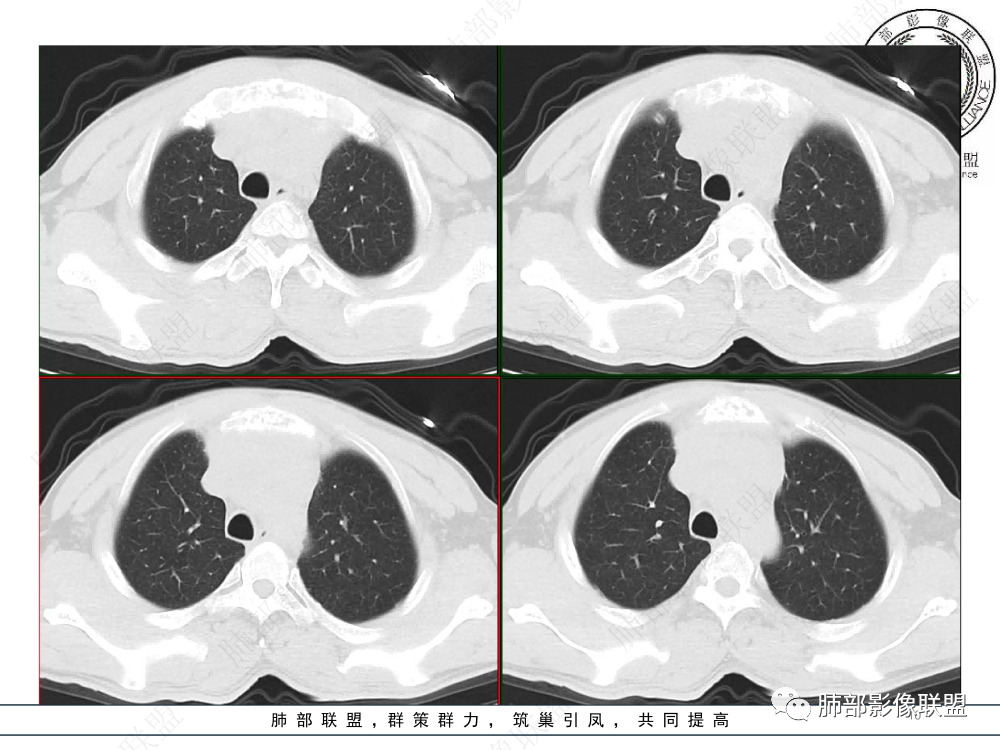

1.临床资料:中老年男性,病史较长-8个月,主诉胸痛,实验室资料:乳酸脱氢酶(LDH)升高。

2.影像表现:前上纵隔较大肿块,密度不均,形态不规则,边界不清,有结节样突起,脂肪间隙显示不清。病灶侵犯左无名静脉及上腔静脉,其中左无名静脉闭塞(胸背部侧支循环明显,亦表明回流受阻)。增强后轻中度不均强化。坏死边界欠清晰。可见心包积液,提示心包受侵犯。右侧上叶及纵隔胸膜下结节影,疑胸膜肺转移可能。胸骨柄后缘皮质不完整,疑骨质破坏(未提供骨窗及矢状位图像)。左锁骨上可见肿大淋巴结。